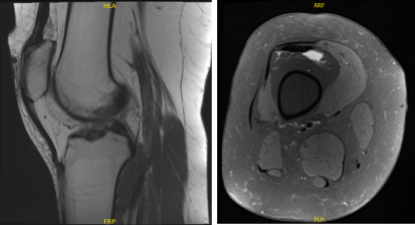

MRI of right knee

Patient returned and presented her MRI- found Tri compartment degenerative chest, with cartilage loss most pronounced in the patellofemoral compartment.

Complex tear involving the anterior horn lateral meniscus with a horizontal component extending into the body lateral meniscus with small joint effusion.